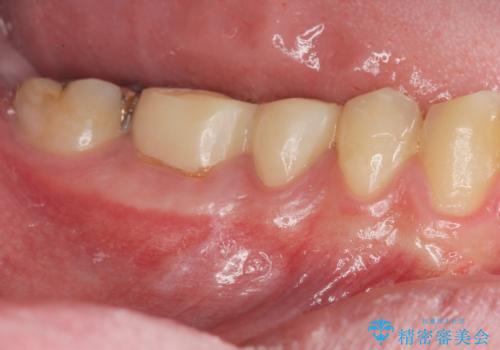

[ 重度の歯周病 ] 骨の造成を伴う奥歯インプラント治療

![[ 重度の歯周病 ] 骨の造成を伴う奥歯インプラント治療の症例 治療前](https://seimitsushinbi.jp/wp/wp-content/uploads/2023/08/dd050296376ce2223375e4fe7c012da0-500x350.jpg?v=1691032235)

![[ 重度の歯周病 ] 骨の造成を伴う奥歯インプラント治療の症例 治療後](https://seimitsushinbi.jp/wp/wp-content/uploads/2023/08/53b97aab07991cb3b8113730db863b4d-500x350.jpg?v=1691032282)